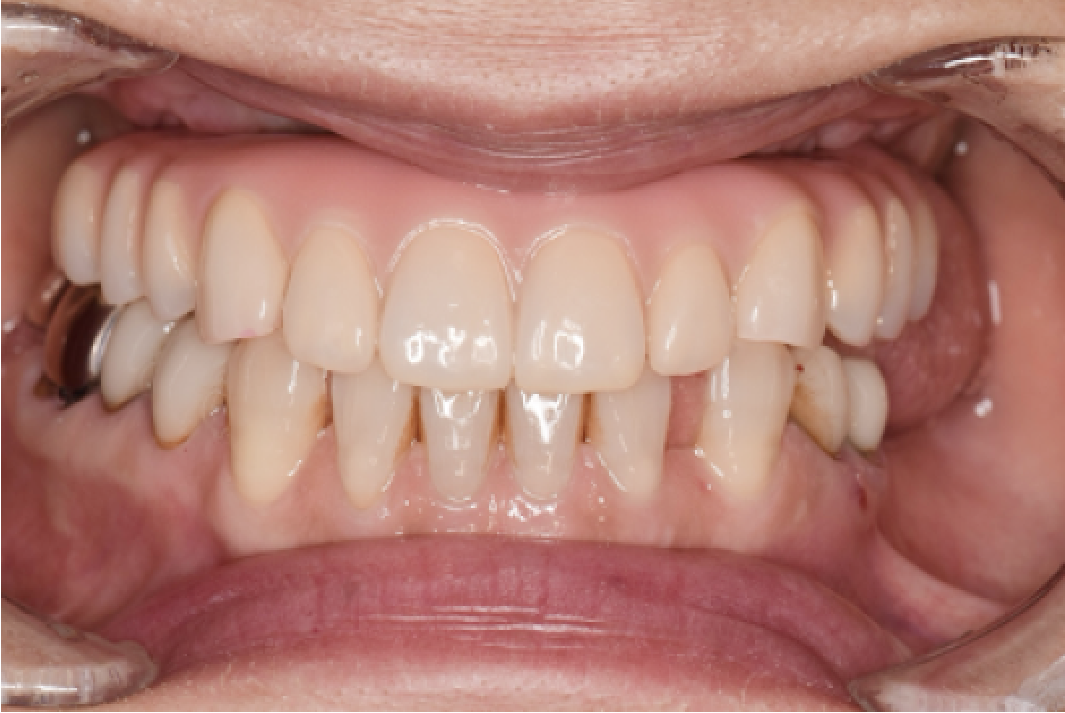

CASE05

■ 治療内容

上下顎All-on-4インプラント治療

■ 治療費用

(モニター)6,610,000円(税込)

■ 治療期間

約9ヶ月

■ リスク

治療後の腫れや出血、またメンテナンスを怠ることで周囲炎のリスクあります。